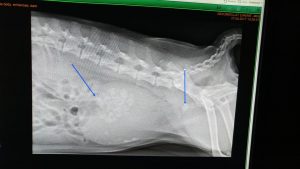

זואי הובהלה למרפאה כשהיא סובלת מחסימה בדרכי השתן. עכשיו תדמיינו שמישהו מונע מכם להשתין לא למשך שעה או שעתיים אלא שעות רבות וממושכות… אי אפשר לתאר את המצוקה שזואי סבלה ממנה כשהגיעה. בצילום רנטגן גילינו ששלפוחית השתן של זואי מלאה באבנים רבות שנוצרו שם, ושמספר אבנים סוררות נדחפו לכיוון היציאה מהשלפוחית וחסמו את האפשרות של זואי לתת שתן. זואי הוכנסה לניתוח דחוף במהלכו נפתחה השלפוחית והאבנים הרבות הוצאו והחסימה שוחררה. זואי התאוששה במהירות מפתיעה והודתה לנו בכשכושי זנב וליקוקים.